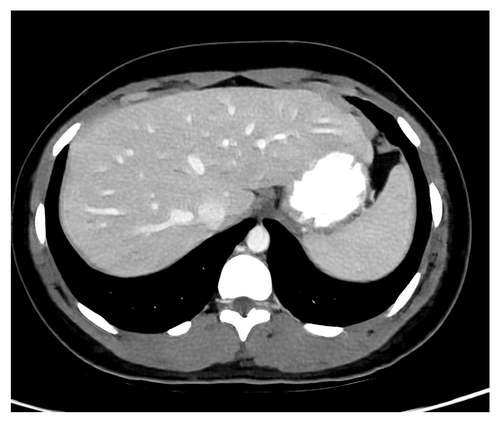

Fig. 9 and 10 show results for Exam 2, a low-contrast clinical exam. Both the full slice and zoomed views show that TMGAN produces a uniform texture for this low-contrast exam, while WGAN-VGG produces a uniform but coarser texture. More importantly, the arrows in Fig. 9(9) and 10(10) show that low-contrast features are best detected using the TMGAN-blended results.